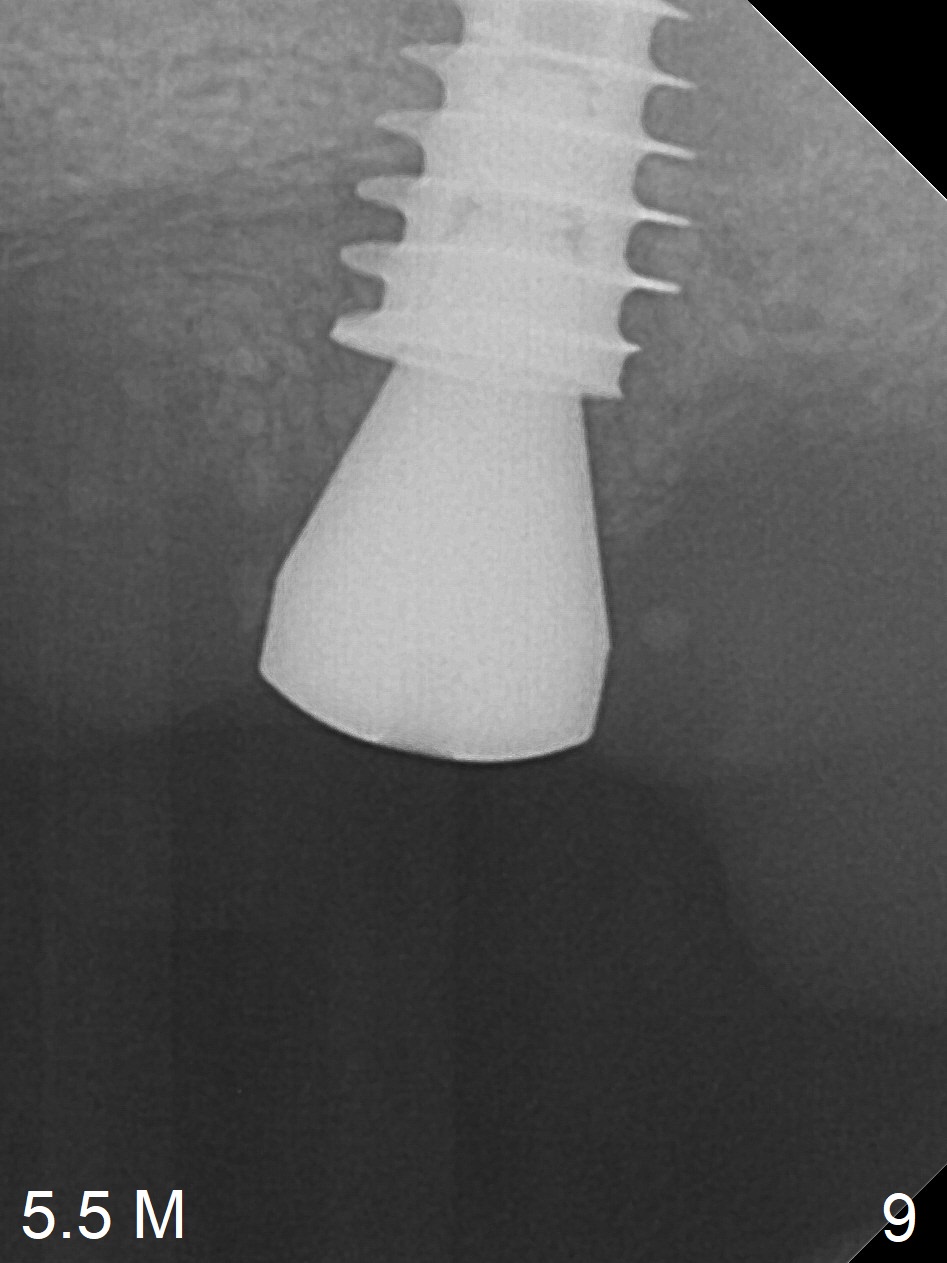

One month later, bone graft is placed mesiopalatal to the implant at #15 (Fig.7 *,8) while a 3.8x13 mm implant is placed at #13 following bone expansion (using Magic Split and Magic Expander 3.0 mm (abutment 5.5x4(5) mm). Another month later, the tooth #16 is extracted to create space for #15 restoration. Two weeks later the abutment at #15 is found to be unstable (2.5 months postop). Local oral hygiene is poor. The abutment is removed and a 6x4 mm healing abutment is placed with mild tenderness. It appears that the limited bone height is associated with low stability with CMC. Three months later (5.5 months postop), the implant seems to be stable (Fig.9,10). The implant remains stable clinically 7 months postop (Fig.11). The bone graft appears to mature and covers the abutment with provisional 24 months postop, the bony changes is related to the thick gingiva (Fig.12 ^).